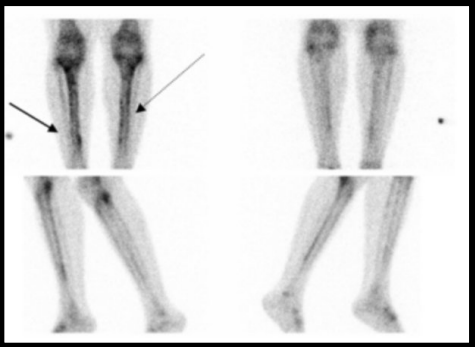

hyperfixation.png

Hyperfixation aux bords antérieur et postérieur à la scintigraphie.